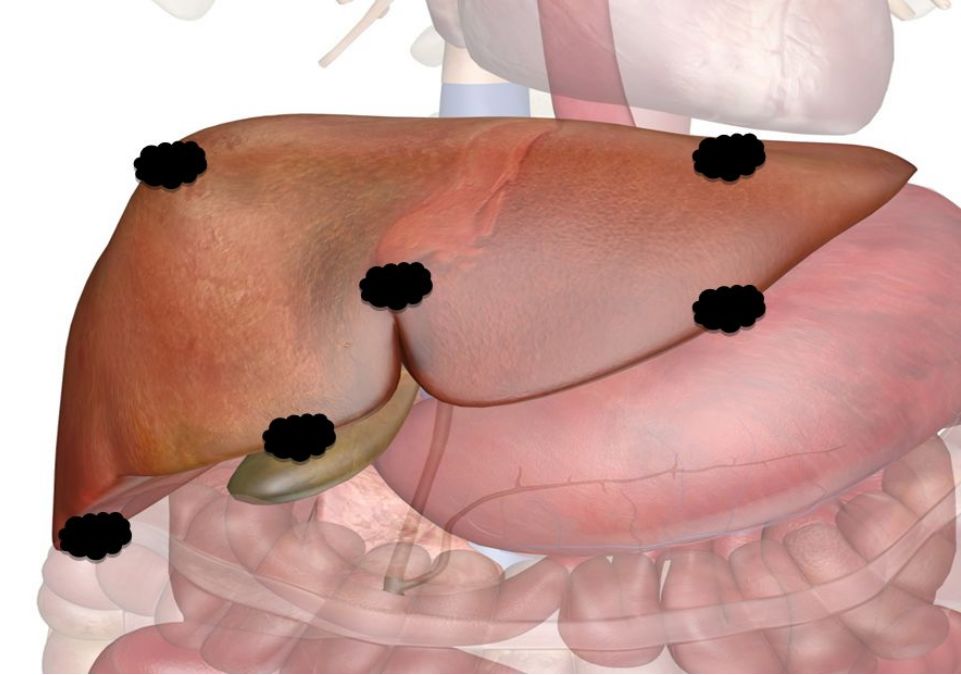

由于肝脏特殊的生理解剖,临近危险器官的特殊部位以及影像显示不清的肝肿瘤,一直是影像引导下经皮消融治疗的难点或“禁区”。 近日,我院放射科介入病房邵海波教授、田玉龙主治医等在麻醉科的大力配合下,为一名复杂的肝癌患者进行了影像引导下的经皮微波消融治疗。手术仅历时1.5小时,术后3天患者即顺利出院。 患者为62岁女性,半年前诊断为原发性肝癌,为肝左叶单发病灶,曾行经导管肝动脉化疗栓塞和微波消融治疗,术后病灶完全灭活。本次入院MRI检查发现新发肿瘤,肝内共有4个活性病灶,分别位于心缘旁、膈顶、胆囊旁等“危险部位”,血供较差,TACE治疗控制不佳,经详细讨论,决定采用经皮微波消融治疗。由于病变位置特殊,加之平扫CT或超声均不能清晰的显示全部病灶,大大增加了消融治疗的难度和风险。术中,治疗团队采用腹水隔离、CT/超声双引导进针监测、解剖标记定位、低功率间断消融等多种辅助手段相结合,对全部4处病灶进行了安全、精准的微波消融治疗,手术历时1.5小时,术后3天患者顺利出院。 图1. 临近心脏的膈顶部病灶,水隔离保护下消融 图2. 临近包膜的膈顶部病灶,水隔离保护消融 图3. 紧邻胆囊病灶,超声引导和监测下低功率间断消融 图4. CT和超声均显示不清的病灶,采用CT引导解剖标记定位消融 图5.肿瘤消融治疗是指利用消融治疗针穿刺肝肿瘤,针尖能够产生电磁波而使周围组织升温至80度以上的高温,从而杀灭肿瘤。 图6.危险部位肿瘤是指当肿瘤靠近膈顶、心脏、胃、肠管、胆囊、以及肝门部等部位时,对肿瘤进行消融就容易损伤相应的器官,引起并发症。因此这些部位的肿瘤称为危险部位肿瘤。 此病例癌症病灶位于膈顶部、心脏旁、胆囊旁、肝门部、大血管附近,肝边缘近胃肠道、外凸近腹壁,治疗难度大,技术复杂、成功率低、风险高。介入病房开展水隔离技术、胆管冷却技术、术中引流技术、造影增强定位技术、解剖标记定位技术、复合影像导航穿刺和监视技术等新技术对危险部位和复杂病灶进行成功的经皮消融治疗,几乎做到肝脏肿瘤消融无禁区、无死角。 近年来,影像引导下经皮微波消融治疗已成为肝癌/肝转移癌、肺癌、肾癌等实体肿瘤最为有效的微创治疗手段之一,具有创伤小、恢复快、疗效确切、可重复治疗等优点。据统计,2018年,放射科介入病房利用各种辅助技术处理复杂或高危部位肿瘤41例,疗效显著且无并发症发生,与前期未应用辅助技术的病例相比,完全消融的比率显著提高(93.5% vs.78.5%),不良反应发生率显著降低。 我院放射科介入病房自2004年开始开展影像引导下肝癌的射频/微波消融治疗,在放射科副主任苏洪英教授的领导下,不断突破技术难点,治疗水平逐年提高。科室选派技术骨干到国外学习先进技术,其中本例手术的术者邵海波教授就是在我院中青年骨干培训计划的支持下,在哈佛医学院/麻省总医院进行了为期近2年的消融治疗培训和研究后,回国将所学更好地应用于临床。目前,科室在影像引导下经皮肝肿瘤微波消融领域处于国内领先水平。